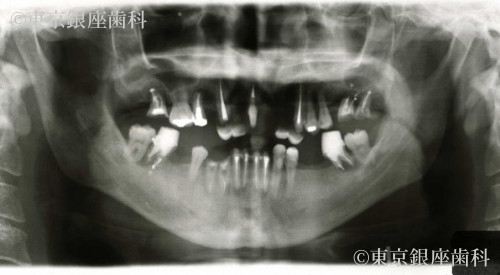

術前に全顎的な重度の歯周病と、多数歯に及ぶ虫歯と根尖病巣によって口腔機能・審美面の著しい低下が認められたが、ワンデイインプラントによって両方の改善を得られた症例

全顎的な重度の歯周病と、虫歯と根尖病巣によって残っている歯のほとんどが予後不良の状態でした。